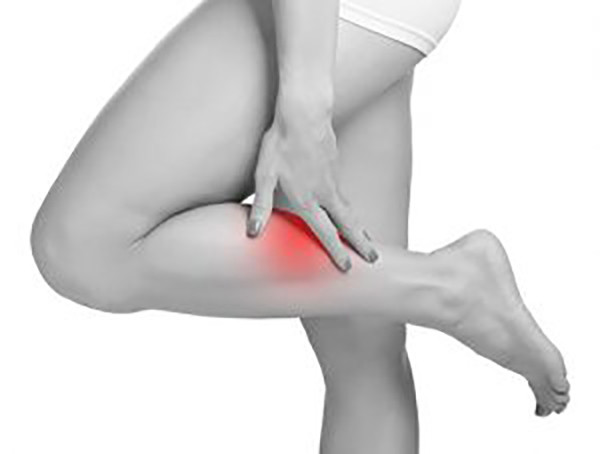

Ciltte renk değişikliğiKolunuzda veya bacağınızda aniden açıklanamayan kırmızı bir leke mi oluştu? Bu, venöz trombozun bir belirtisi olabilir. Bu renk değişimi olan bölgenin sıcak ve yumuşak olduğunu mu hissediyorsunuz? Bu belirti, derinin altında bir kan pıhtısı olduğunu gösterebilir.

Kollarda veya bacaklarda ağrıKollarınızda veya bacaklarınızda nispeten masum bir ağrı veya kas krampı gibi görünebilir, ancak dikkatli olun. Yürümeye veya esnemeye başladığınızda ağrı daha da kötüleşiyor mu? Durum buysa ve cildiniz de kırmızı ve şiş görünüyorsa, bir uzmana danışmanızda fayda var.